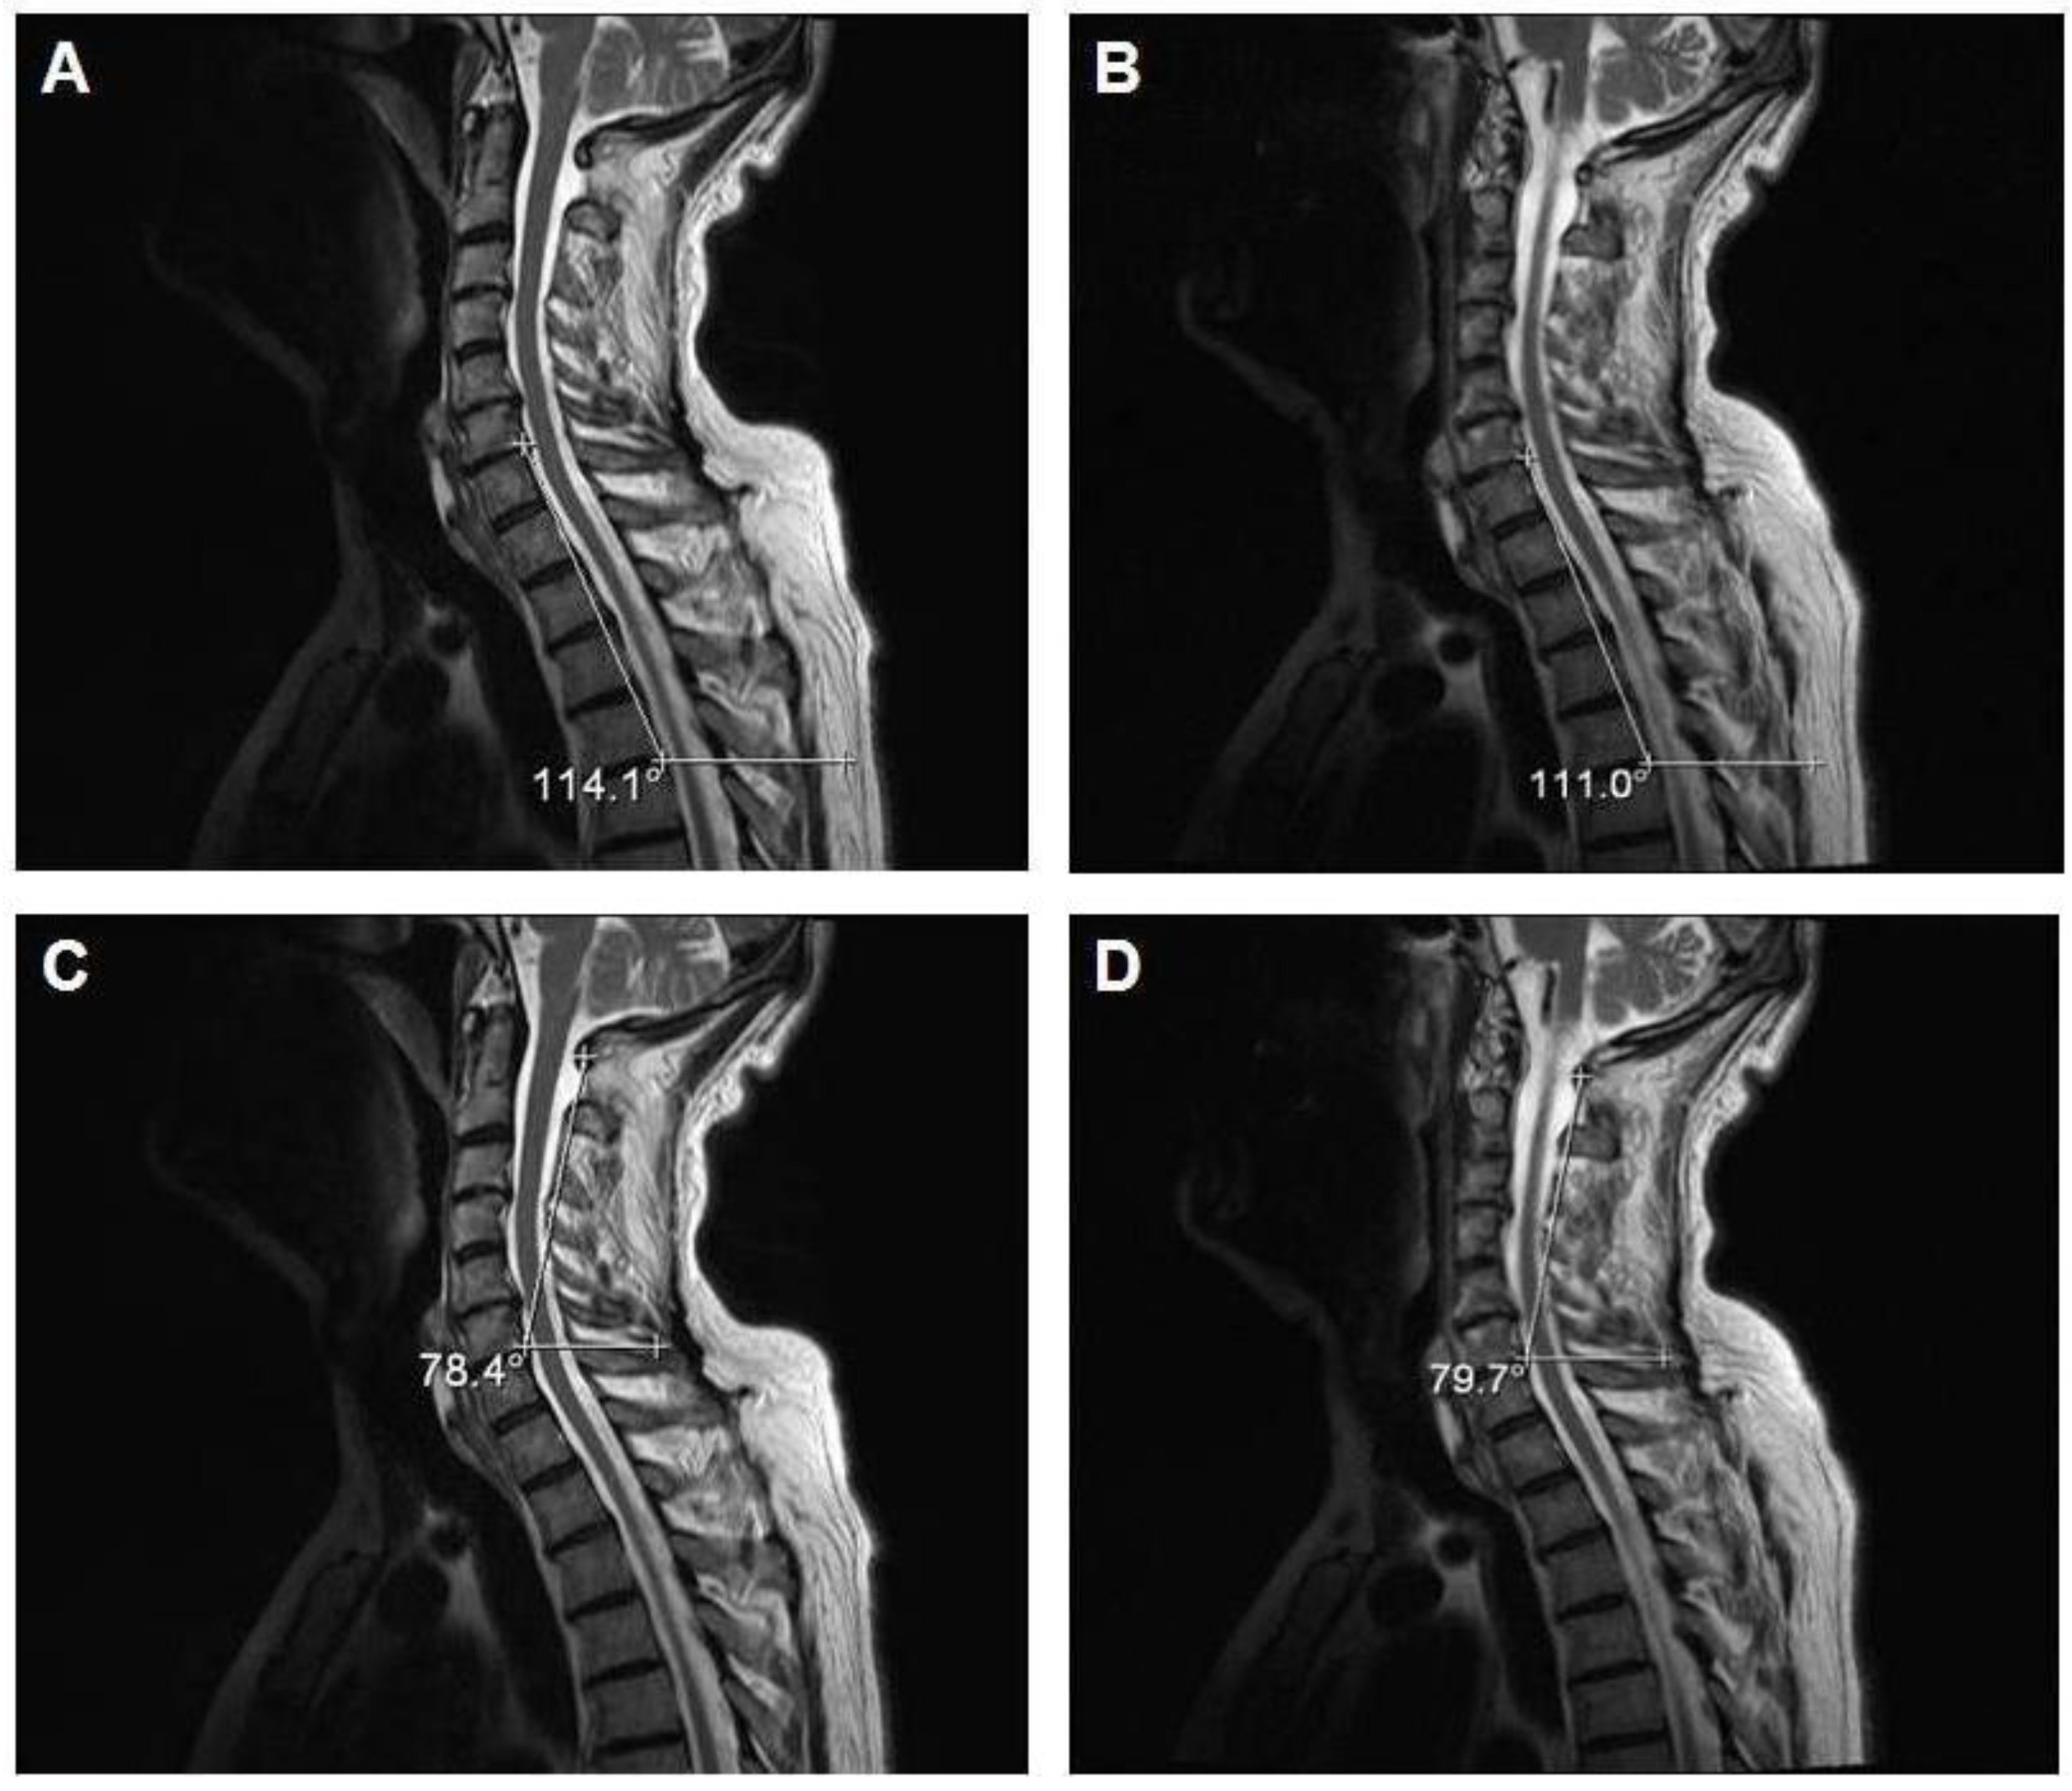

Figure 3 shows the MRI results of one of the three subjects (64 years) who was trained for 30 days with the Angel’s Wings. The figure shows the post-training variations in the curvatures of the cervico-dorsal (see Figure 3B) and cervical (see Figure 3D) column compared to those of the pre-training (see Figure 3A,C).

Figure 3.

Pre-exercise (A and C) and post-exercise (B and D) magnetic resonance imaging (MRI) images (sagittal T2 weighted fast spin echo images; TR/TE-4000/105) of one representative subject who performed the motor task daily (morning and evening) for a duration of 30 days.

In subjects who perform motor tasks daily (morning and evening) for 30 days, via MRI images, we demonstrated a realignment of the cervico-dorsal column between the pre- and post-training phases due to a variation of only a few degrees in its curvatures. Moreover, an improvement in posture is shown because, additionally, the gibbus, caused by a kyphotic posture, appears blunt. This data is important, considering the fact that the training period was 30 days, a relatively short period of time.